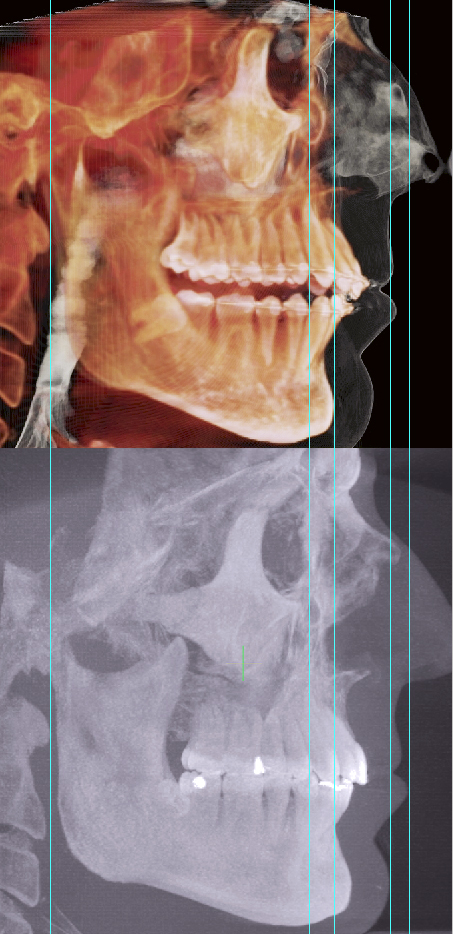

Your maxilla will come forward without surgery. As it comes forward, the bones around your condiles will rotate and your jaw will become loose and drop forward. Therefore, you will not be pulling JUST the maxilla forwards and end up looking like an inbred retard. Not only your maxilla will come forward but YOUR ENTIRE FACE WILL! Especially your cheekbones, so if you don't have cheekbones, you will get them with this technique. Your whole face will come forward and your jaw will follow along getting rid of TMJ forever! Below are my results...

|